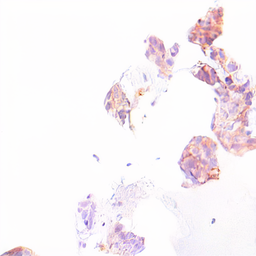

Refer to captionRefer to captionRefer to captionRefer to captionRefer to captionRefer to captionRefer to captionRefer to captionRefer to captionRefer to captionRefer to captionRefer to captionRefer to captionRefer to captionRefer to captionRefer to captionRefer to captionRefer to captionRefer to captionRefer to captionRefer to captionRefer to captionRefer to captionRefer to captionRefer to captionRefer to captionRefer to captionRefer to captionRefer to captionRefer to captionGenerated - HER2Generated - CATCHStylesStylesLayoutsLayouts

Figure 8: Image generation results for the histopathological dataset with nearby style sampling. Shown are cases where tumor is present in the layout (white: tumor, black: non-tumor tissue and slide background), but no tumor tissue is present in the style images.

In Fig. 8, we provide examples of image generation for the histopathological datasets in cases where style information is missing in the style query images. The generated images exhibit realistic tissues, but the style is determined by the model and reflects styles from the training style distribution.

This scenario primarily arises in nearby style sampling, where only a single style query image is used. We see these cases as noncritical as they do not result in invalid images, and they highlight that the model falls back to plausible styles if it cannot extract style information from the style query images.